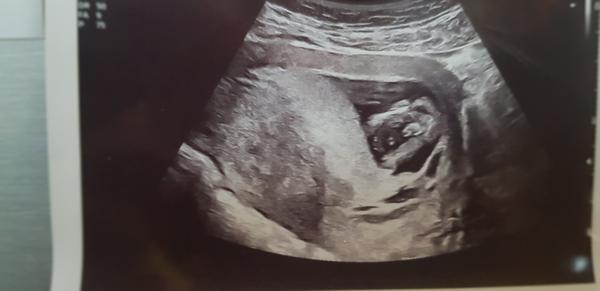

@adelaide131 to víte že může aspoň tedy muj případ tohle jsem viděla v 15tt a od té doby údajně opět holka ja bych si zase z celého srdce přála konečně syna ale neni nam dáno 😪